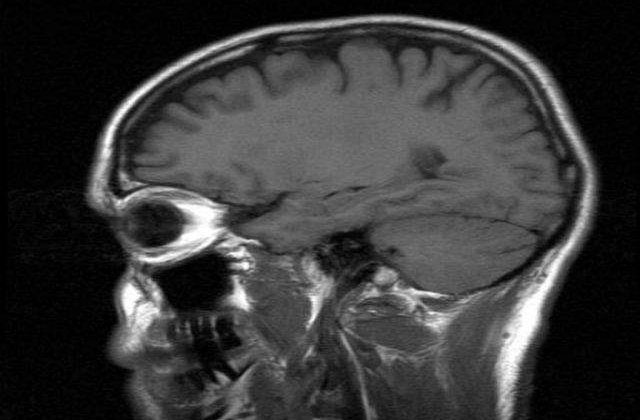

In Romania, acest tip de explorare a fost initiata in cadrul unui proiect de cercetare multidisciplinar, desfasurat prin Universitatea Bucuresti, Facultatea de Fizica, in colaborare cu echipele de medici din Centrul de Exploare a Epilepsiei din Sectia de Neurologie a Spitalului Universitar si sectia de Neurochirurgie Functionala din Spitalul "Bagdasar Arseni".

"Succesul metodei este datorat unei munci de planificare neurochirurgicala foarte minutioasa. Folosim software si algoritmi moderni de neuronavigatie, care permit pozitionarea corecta a electrozilor si evitarea vaselor de sange. In acest fel, electrozii exploreaza focarul epileptic itr-o maniera tridimensionala oferind date extrem de precise", spune directorul proiectului de cercetare, profesorul Andrei Barborica.